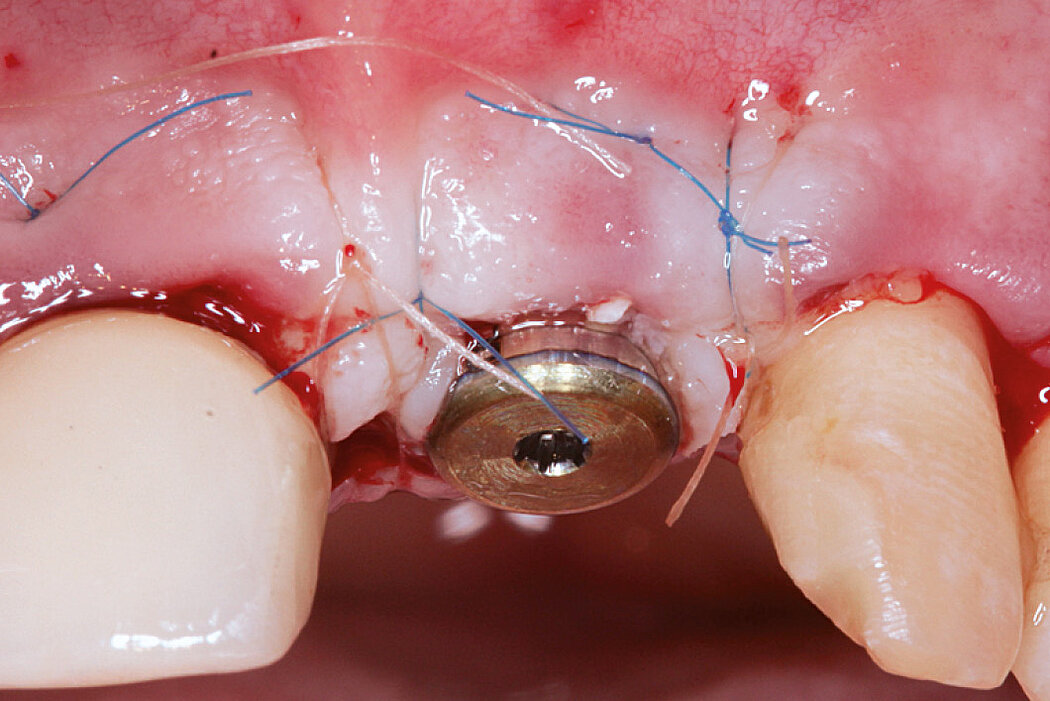

Aim / Approach

Reconstruct alveolar bone with severe vertical loss from chronic periodontitis at the lower left second molar. Investigate the clinical and histological result by using Geistlich Combi-Kit Collagen after tooth extraction.

Conclusion

The defect was completely filled with newly-formed hard tissue after 6 months. Histomorphometric analysis revealed 45% of the hard tissue area including bone substitute material and 28% of the soft tissue area.